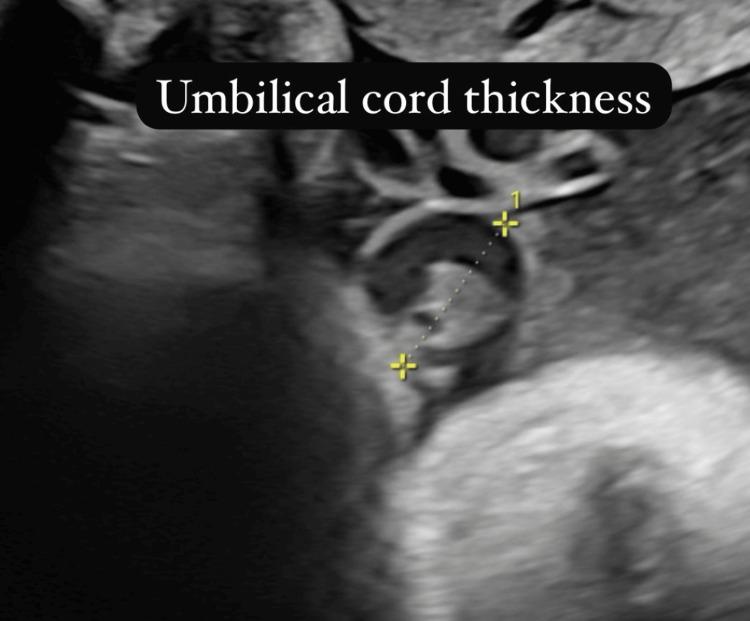

超声测量脐带厚度、胎儿脂肪层和室间隔厚度作为妊娠期糖尿病孕妇胎儿巨大儿预测指标的前瞻性研究。

Prospective Study on Sonographic Measurement of Umbilical Cord Thickness, Fetal Fat Layer, and Interventricular Septal Thickness as Predictors of Macrosomia in Fetuses of Women With Gestational Diabetes Mellitus.

Fetal macrosomia is a common and concerning complication of gestational diabetes mellitus (GDM), associated with increased risks for both maternal and neonatal morbidity. Traditional methods of predicting macrosomia often lack precision, particularly in diabetic pregnancies. This study aimed to evaluate the efficacy of three sonographic parameters, umbilical cord thickness (UCT), fetal fat layer (FFL), and interventricular septal thickness (IVS), as predictors of fetal macrosomia in women with GDM.

MATERIALS AND METHODS

This prospective study included 123 pregnant women with GDM between 34 and 40 weeks of gestation. Comprehensive maternal data, including body mass index (BMI) and glycemic parameters (fasting blood sugar (FBS), postprandial blood sugar (PPBS), and glycated hemoglobin (HbA1c)), were recorded. Sonographic measurements of UCT, FFL, and IVS were performed and analyzed for their association with birth outcomes. Macrosomia was defined as a birth weight greater than 4000 g.

RESULTS

Macrosomia occurred in 62.6% of pregnancies, with strong associations with maternal BMI (p<0.001) and HbA1c levels (p<0.001). Sonographic parameters showed significant correlations with birth weight: UCT (r=0.792, p<0.001), FFL (r=0.34, p<0.001), and IVS (r=0.295, p=0.001). A UCT ≥25 mm demonstrated excellent sensitivity (93.3%) and specificity (85.4%) for predicting macrosomia. FFL ≥4.5 mm showed high specificity (93.3%) and positive predictive value (PPV) (97.3%), while IVS ≥3.9 mm exhibited good specificity (85%) but lower sensitivity (71.8%). Despite the high prevalence of macrosomia, 88.6% of deliveries were uncomplicated, though the cesarean section rate was high (64.2%).

CONCLUSION

Sonographic measurements of UCT, FFL, and IVS are valuable predictors of fetal macrosomia in GDM pregnancies. UCT, in particular, demonstrated the strongest correlation with birth weight and superior diagnostic accuracy. The integration of these sonographic parameters with maternal factors can enhance the accuracy of macrosomia prediction, potentially improving clinical decision-making and optimizing maternal and neonatal outcomes.